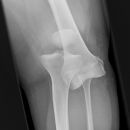

Tibiakopffraktur (nicht disloziert)

Es wurden keine Bilder gefunden.